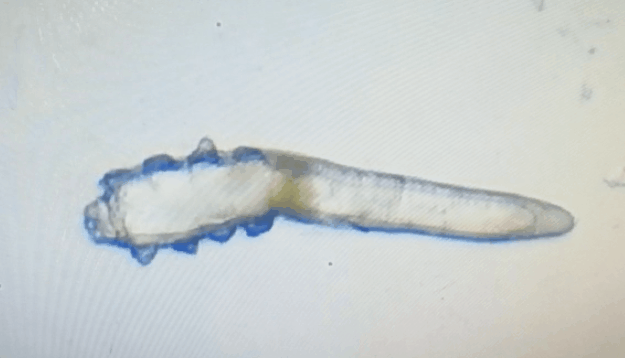

廈門眼科中心眼表及角膜病專家商旭敏博士指出:蠕形螨中的毛囊蠕形螨和皮脂蠕形螨可寄居于人體。在眼部,毛囊蠕形螨常寄居于睫毛囊,而皮脂蠕形螨多寄居于眼瞼皮膚的皮脂腺和瞼板腺。蠕形螨瞼緣炎是蠕形螨感染瞼緣所致的慢性炎性反應(yīng)性疾病,主要累及瞼緣皮膚、睫毛囊和腺體以及瞼板腺,以眼癢、眼異物感、眼干、瞼緣充血、鱗屑及睫毛根部袖套狀分泌物等為典型臨床表現(xiàn),嚴(yán)重者可引起結(jié)膜及角膜并發(fā)癥,該病可能具有一定的傳染性。

蠕形螨會(huì)引起睫毛異常,引發(fā)瞼緣炎性反應(yīng),瞼板腺堵塞,引起結(jié)膜炎、角膜炎等并發(fā)癥,嚴(yán)重的話將發(fā)生角膜穿孔致視力損傷甚至失明。